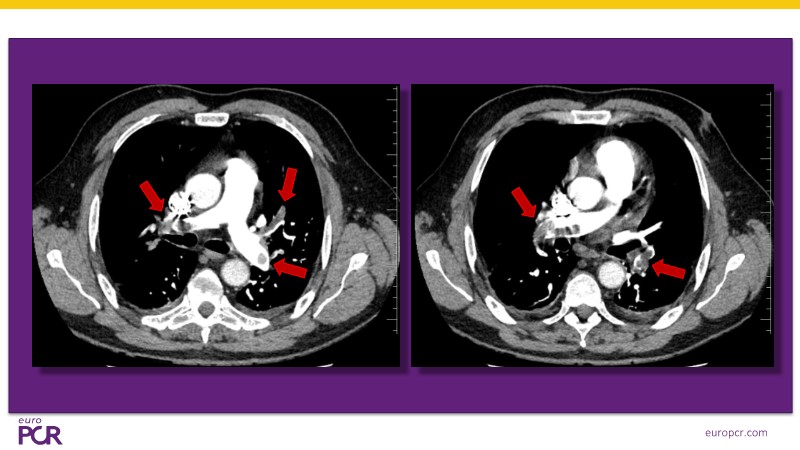

Discover a streamlined approach to pulmonary embolism treatment in this EuroPCR 2025 session. Learn how ultrasound-assisted thrombolysis improves right ventricular function and pulmonary perfusion while enabling timely reperfusion with low-dose thrombolytic therapy delivered directly to the clot. Explore the latest data from the HI-PEITHO randomised trial and review real-world cases that highlight patient selection and the practical application of catheter-based reperfusion strategies. With its minimally invasive profile, low complication rates, and straightforward logistics, the EKOS system offers a clinically sound and efficient solution to PE management.